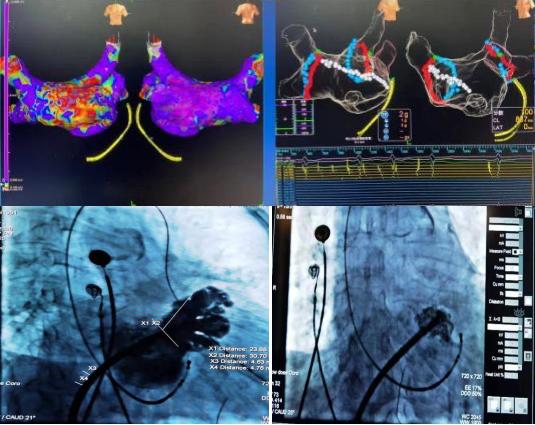

2020年12月30日,延安大學(xué)咸陽醫(yī)院心血管內(nèi)七病區(qū)成功開展一例射頻消融+左心耳封堵一站式介入手術(shù)。該種微創(chuàng)手術(shù)既可以解決患者房顫癥狀問題,又能預(yù)防房顫腦卒中的風(fēng)險(xiǎn),將卒中和出血風(fēng)險(xiǎn)降到最低。一消一封,兩種手術(shù),一站結(jié)合,一勞永逸。

78歲高齡的杜奶奶,受到房顫疾病困擾多年,從寶雞慕名來到我院。經(jīng)我科高勝利主任、賀新榮責(zé)任總醫(yī)師及徐云鵬主治醫(yī)生的詳細(xì)檢查與謹(jǐn)慎的決策,同時(shí)在心血管病院吳棟梁院長、張玉順教授和電生理同仁的協(xié)助下,成功地進(jìn)行了一站式手術(shù)。該手術(shù)分兩部分進(jìn)行,首先是行房顫射頻消融術(shù):房顫射頻消融手術(shù)可最大限度地使患者恢復(fù)竇性心律(正常心律);第二部分是行左心耳封堵術(shù):左心耳封堵術(shù)是目前全球預(yù)防房顫患者卒中的治療新趨勢(shì),它能有效減少病人的病死率、致殘率,同時(shí)減少出血的發(fā)生。兩種手術(shù)一站式結(jié)合,“一消一封”,“一勞永逸”。手術(shù)過程順利,術(shù)后患者轉(zhuǎn)復(fù)為竇性心律,左心耳封堵傘完全展開,造影顯示無殘余分流?;颊吒黜?xiàng)生命體征平穩(wěn),順利返回病房。在主管護(hù)師趙燕子的全程指導(dǎo)下,護(hù)理團(tuán)隊(duì)從患者臥位-飲食-運(yùn)動(dòng)-心理進(jìn)行全方位的護(hù)理。新年的第4天,杜奶奶恢復(fù)情況良好,順利出院。她笑著說:“我好了,我好了,太謝謝你們了”!